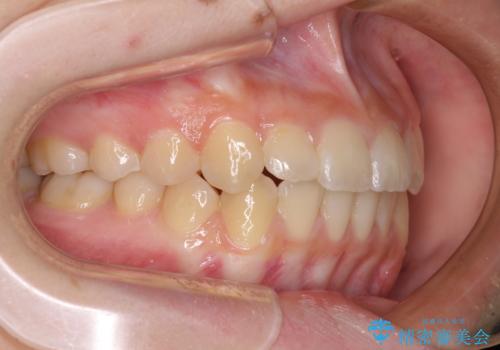

前歯のクロスバイト メタル装置での矯正治療

- 前歯のクロスバイトを気にして来院された患者様です。

前歯の叢生を解消するスペースを獲得するために上顎左右の親知らずを抜歯し、メタルブラケットにて矯正治療を行うこととしました。

当初は1年半程度の治療期間を想定していましたが、上下の正中を合わせていく過程で奥歯の咬みにくさが続いてしまい、2年以上の治療期間を要することとなりました。